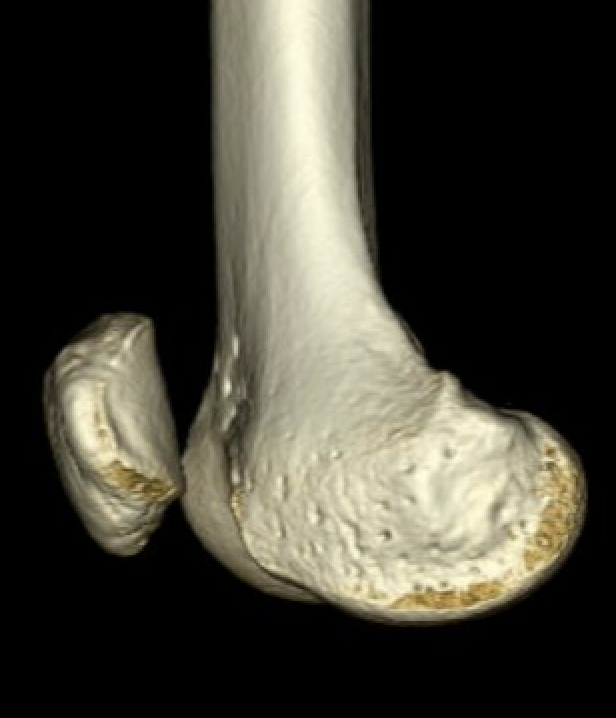

CT

Osteochondral fracture of the lateral femoral condyle

Large osteochondral fracture lateral femoral condyle